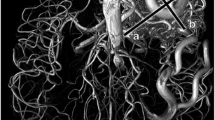

In another case, a 4-year-old girl was found on eye exam to exhibit morning glory optic disc (Fig. 3). Dysplastic, aneurysmal appearance of bilateral ICA was appreciated on both pTOF and cTOF images; however, peripheral vasculature was better delineated with cTOF in this case. Digital subtraction angiography (DSA) subsequently confirmed aneurysmal dilatation of the left ICA.

A 4-year old girl with morning glory optic disc on eye exam. Both pTOF and cTOF demonstrate dysplastic and aneurysmal appearance of the bilateral ICA (arrows). 3D rotation view from DSA confirms aneurysmal dilatation of the left ICA. Note more peripheral vascular delineation is more robust for cTOF (*) compared to pTOF